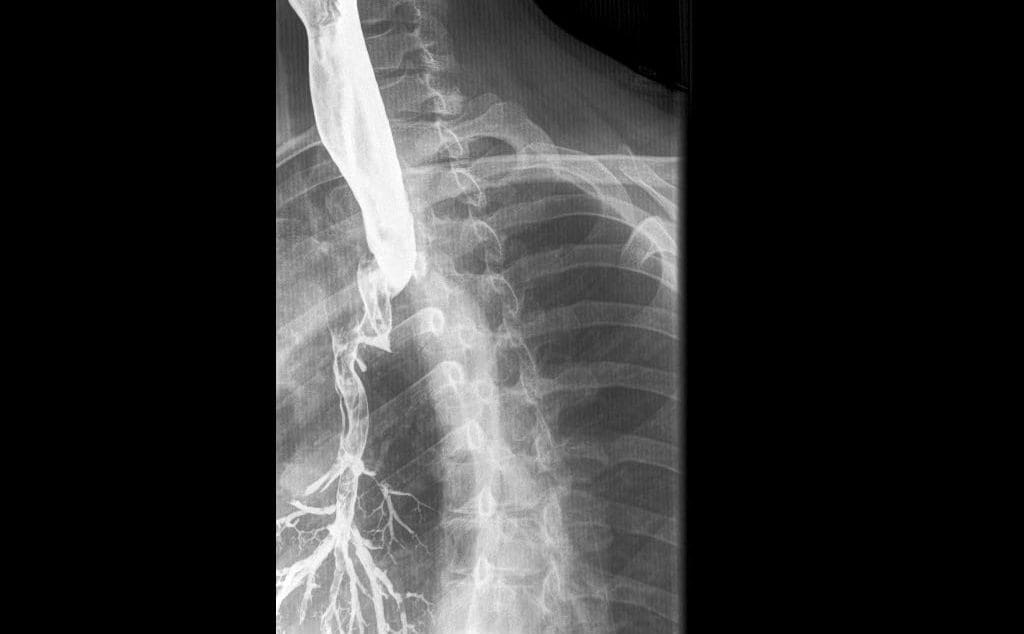

Home Perforations, fistulas and aspiration:  Special considerations for Modified Barium Swallow Studies (MBSS) acquired-tracheo-oesophageal-fistula

acquired-tracheo-oesophageal-fistula